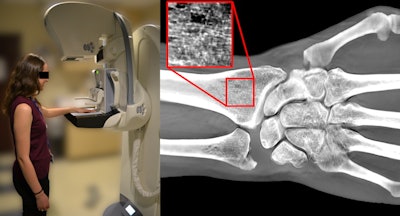

After confirming ex-vivo feasibility, the team recruited five patients, ranging in age from 19 to 75, to undergo wrist tomosynthesis scans. To acquire the digital wrist tomosynthesis (DWT) images, the patients aligned their nondominant, left hand on a generic hand template the researchers taped to a DBT machine.

Left, a 19-year-old woman undergoing a wrist imaging using a DBT scanner. Right, DWT image of same patient. Image courtesy of Yener Yeni, PhD.The team acquired DWT images three times, repositioning the patients' arms to acquire views from different angles. The researchers then used computer calculations to quantify bone mineral density metrics from the DWT images.